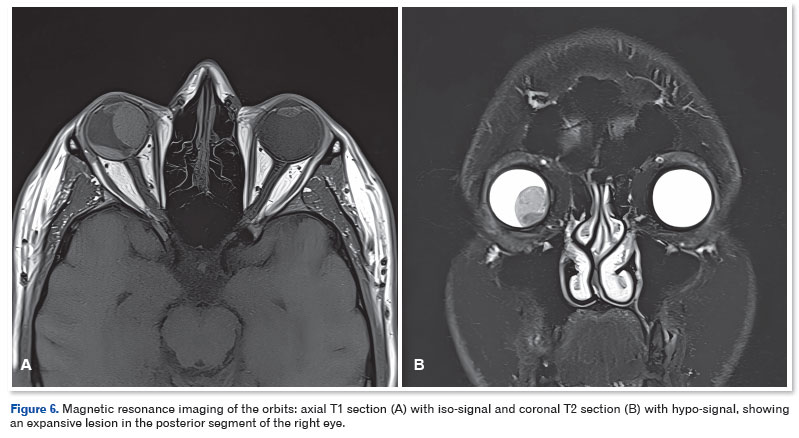

Magnetic resonance imaging (MRI) of the orbits confirmed an expansive lesion in the posterior segment of right eye, with iso-signal on T1 and hypo-signal on T2, with no visible extraocular infiltration (Figure 6). Systemic and laboratory tests ruled out metastases or systemic abnormalities. Due to rapid progression of the lesion and lack of prognosis for vision, a decision was made to enucleate right eye.

Differential diagnosis is challenging, including other ciliary body masses, such as melanoma, nevus, adenoma, and epithelial adenocarcinoma1. In the case reported herein, US and MRI of the eye were fundamental in characterizing the extent and location of the lesion. The imaging characteristics, such as the absence of angle kappa on US and iso-signal on T1-weighted MRI, were not typical of melanoma. However, due to the rapid growth, severe visual impairment, and lack of effective therapeutic alternatives, enucleation was the chosen treatment.